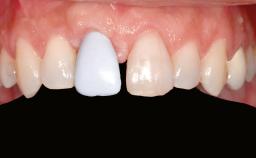

| Prosthesis Type | FDP |

| Provisional Implant-Supported Prosthesis | Prosthodontic margin < 3 mm apical to mucosal crest Prosthodontic margin < 3 mm apical to mucosal crest |